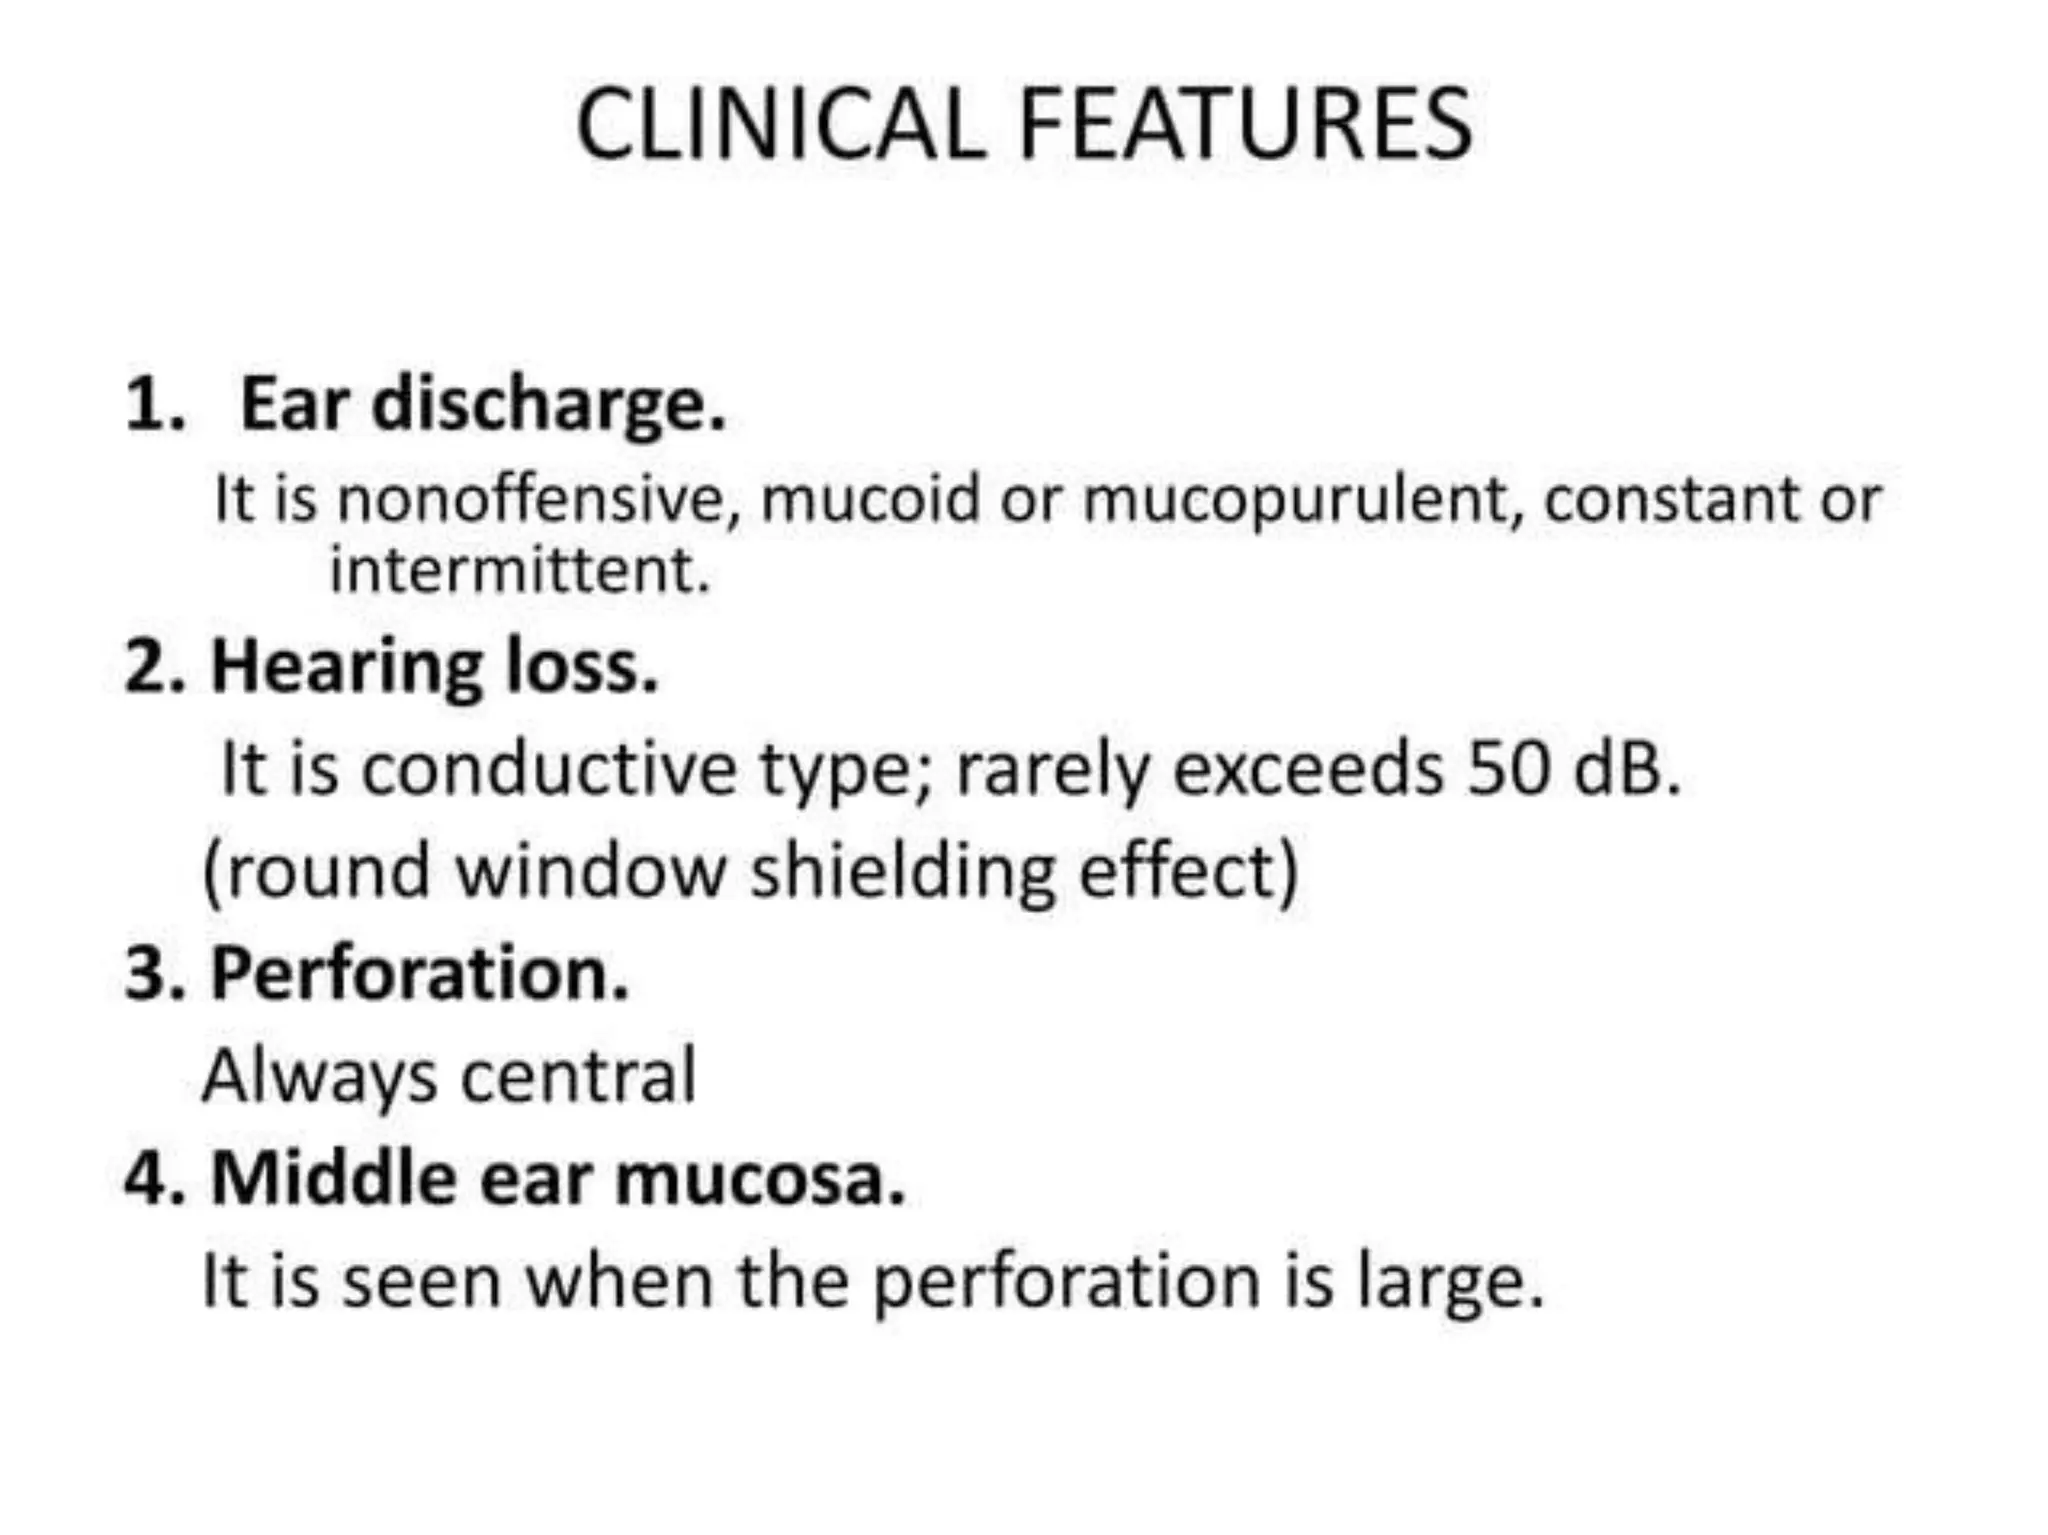

Chronic otitis media is a chronic inflammation of the middle ear and mastoid cavity that presents with recurrent ear discharge through a perforated eardrum. It has several subtypes depending on the state of the eardrum perforation and epithelium. It can be caused by prior acute otitis media, genetics, environment, eustachian tube issues, gastroesophageal reflux disease, craniofacial abnormalities, or immune deficiency.